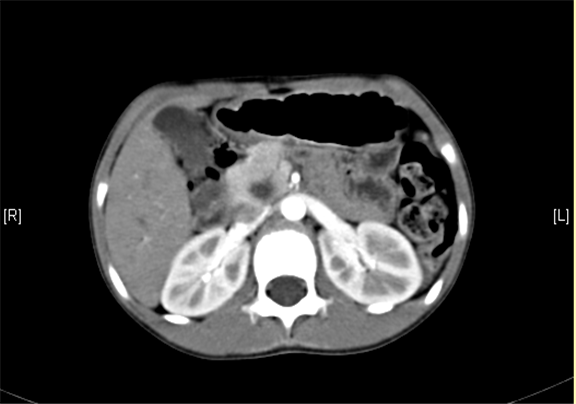

上腹部增强CT:肝内外胆管扩张,考虑胆管囊肿(以左右肝管、肝总管及胆总管扩张明显)可能性大。

术前CT检查:

平衡期